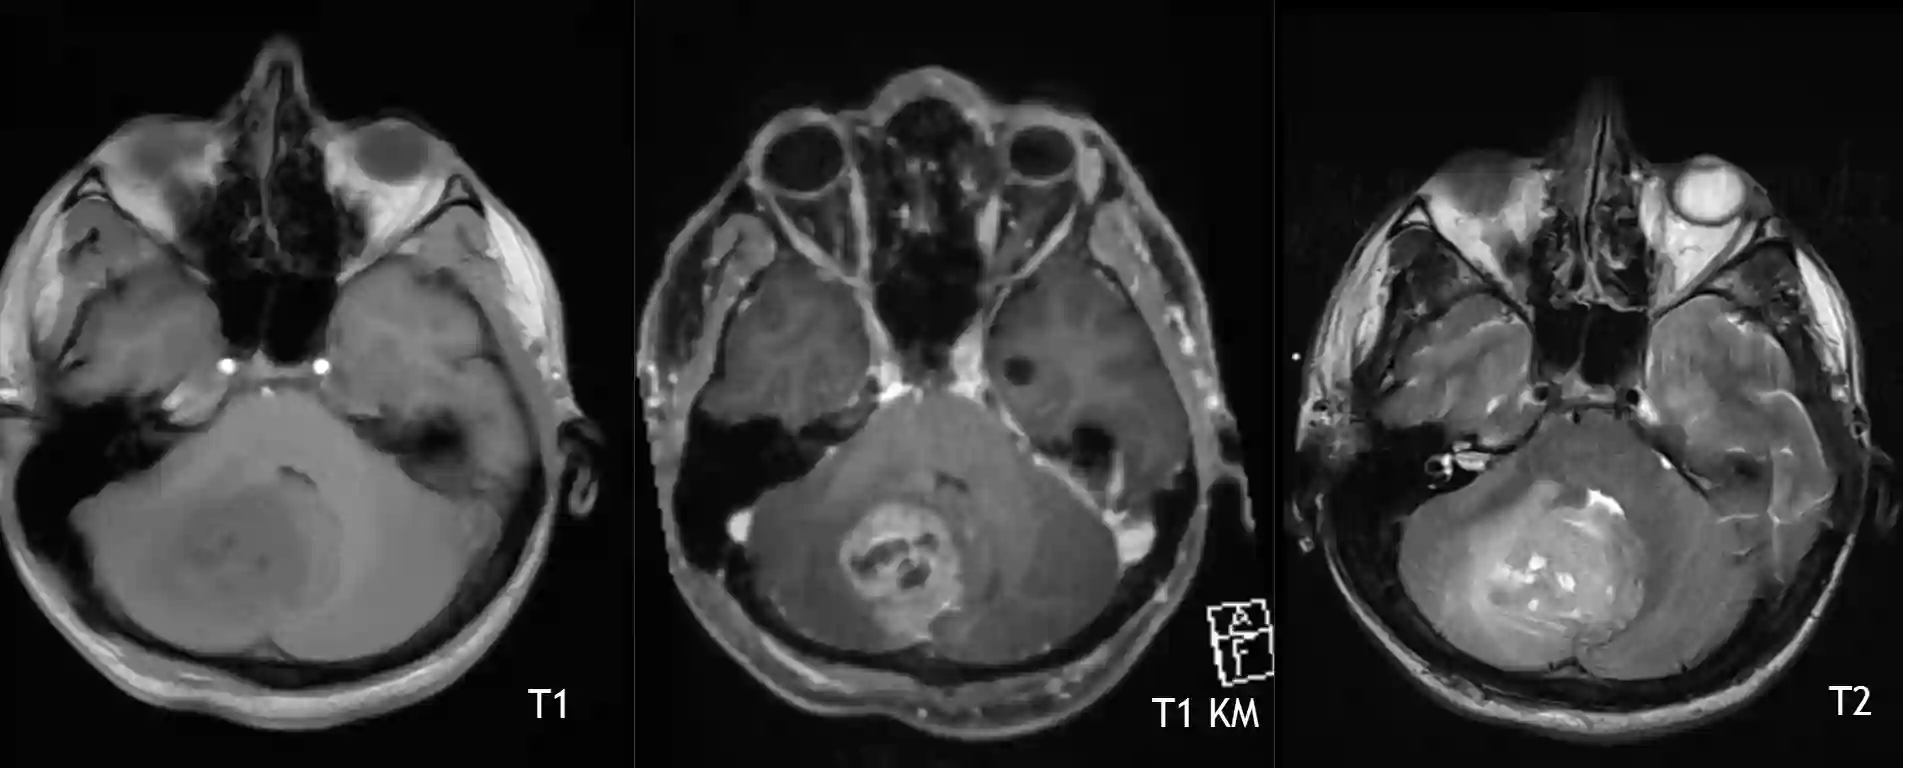

Medulloblastom im Cerebellum

Medulloblastom im Cerebellum in einer T1, T1 Kontrastmittel und T2 Sequenz im MRI.